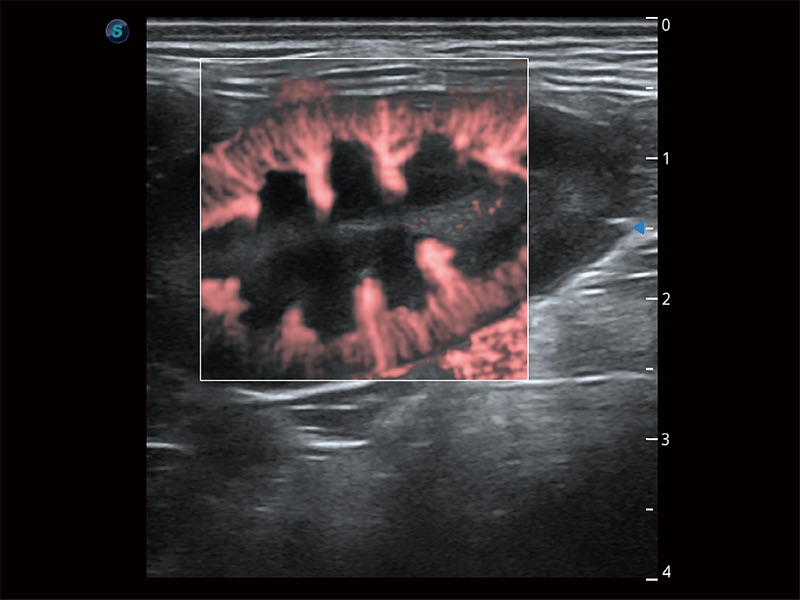

极大提升超低速微细血流的检出能力,同时更精准地滤除软组织和超声信号,为兽用医生提供以往无法通过常规血流获得的疾病诊断信息。